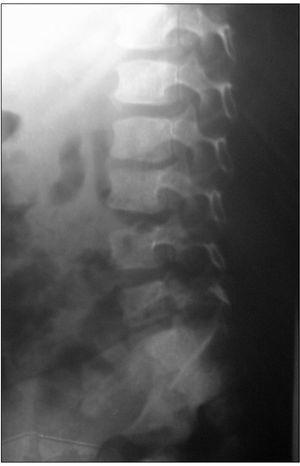

Las técnicas diagnósticas de imagen empleadas se detallan en la tabla 2. La radiografía convencional se realizó en 15/20 pacientes, mostrando alteraciones en diez, siendo el hallazgo más frecuente la disminución del espacio intervertebral (fig. 1). La gammagrafía mostró hipercaptación del radiofármaco en 14 de los 15 casos en que se realizó (fig. 2). La resonancia magnética (RM) se realizó a 15 de los 20 pacientes. La lesión predominante fue la afectación del disco intervertebral con erosiones de los platillos vertebrales adyacentes. En al menos 5 pacientes se objetivaron lesiones de partes blandas y abscesos paravertebrales (fig. 3). En 2 pacientes la afectación vertebral fue múltiple (dos o más espacios), habiéndonos referido en la localización al más afectado. Se realizó una tomografía computarizada (TC) en 6 casos, si bien uno de ellos fue abdominal por síntomas de estreñimiento y dolor abdominal. En 3 niños se realizó punción del disco intervertebral guiada por TC que no aportó aislamiento del germen en ningún caso.

Figura 1. Disminución del espacio discal L3-L4.